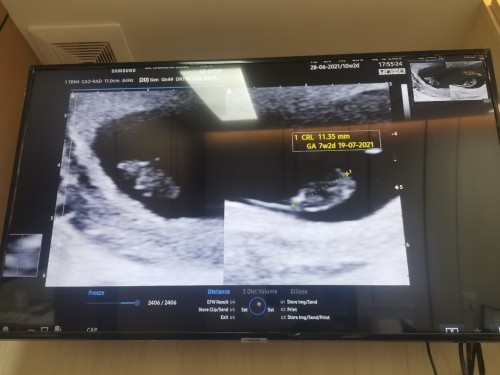

หลังจากที่ตรวจครรภ์เจอ 2ขีด..จนวันนี้ก้น่าจะประมาน 2 เดือนกว่า.. วันนี้ไปฝากครรภ์มาหใอซาวน์หน้าท้อง.. และพบว่า.. ขนาดของเด็กในท้องประมาณแค่เดือนกว่าๆ.. และไม่พบเสียงหัวใจด้วยค่ะ.. หมอเลยให้ยามากิน.. และนัดอรกที.. อีก 2 อาทิตย์ค่ะ.. น้ำตาจะไหลตั้งแต่ตอนรับยาเลยค่ะ.. เรากลัวว่าจะเสียลูกไป คุยกับแฟนที่เข้มแข็งมาก.. เขาก้ปลอบไม่ให้คืดมาก.. หากอีก 2 อาทิตเจอเหมือนเดิมก้ต้องทำใจ..หากครรภ์ไม่สมบูรณ์..แล้วยังให้เขาเกิดมา..เขาจะทรมาน.. มีแม่ท่านไหนเคยเจอแบบนี้มั้ยคะ